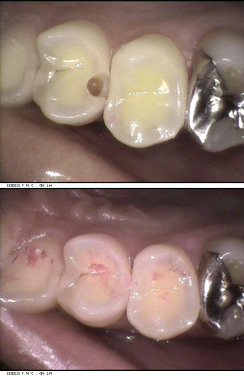

当クリニックでは、口腔内カメラを使用することで、鏡などでは確認しにくい、お口の中の状態(虫歯の状態・治療中や治療後の状態・歯石や歯垢の付き具合など)をモニターで見ることができます。「百聞は一見に如かず」です。丁寧な説明をします。